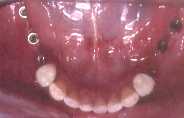

Dum 25 jaroj ŝi restis sen la antaŭaj dentoj, kaj pro tio la superaj postaj dentoj malsupreniris. Do mi devis fari kirurgion por suprenirigi la dentojn. Post la ostointegriĝo de siaj implantoj, oni malfermis la gingivon, faris provizorajn plantajn dentojn, kaj fine ŝi ricevis porcelanajn kronojn. Kaj nun ŝi povas perfekte ne nur manĝi sed amkaŭ ridi, prelegi, kaj eĉ preĝi sen la timo, ke la dentoj povu fali.

Bildo 8 ![]()

25 jarojn sen la malantaŭaj dentoj,